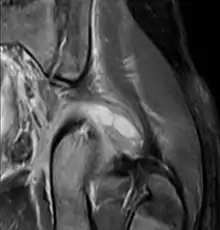

![]() أشعة مقطعية محورية على مستوى T1 توضح التهاب العضلات التقيحي الناتج عن الاصابة بالبكتيريا المكورة العنقودية الذهبية التي تستجيب للميثيسلين. ]] | |

يعتمد تشخيص التهاب العضلات التقيحي على الفحص الاكلينيكي والتاريخ المرضي للمريض. ويظل التصوير بالرنين المغناطسي هو الفحص الأكثر دقةَ لتحديد الإصابة بهذا المرض.[3]